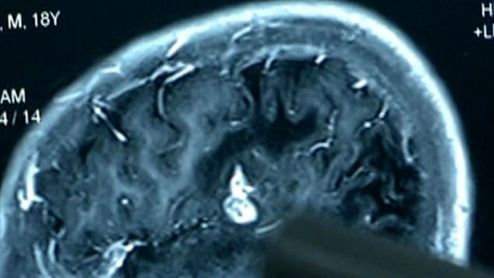

پیداشدن انگل ۱۲ سانتی در مغز مرد جوان! +فیلم

انگلی که به مدت ۱۷ سال در مغز یک مرد چینی زندگی می کرد توسط پزشکان بیرون آورده شد.